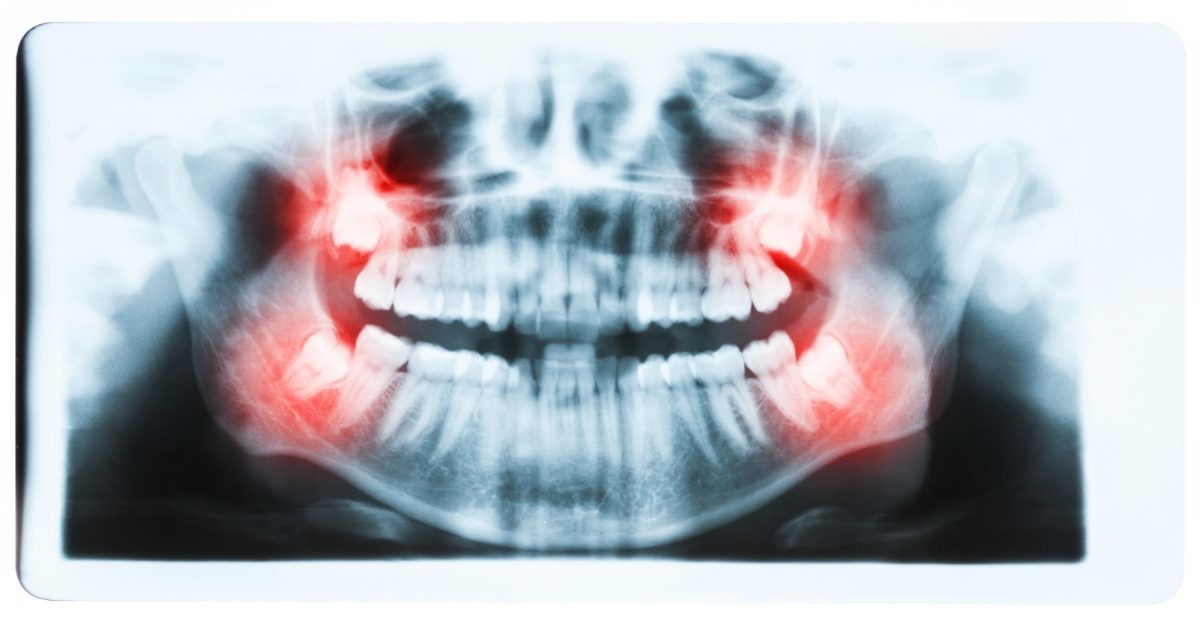

Oral biofilms, a concern for all dental professionals

Biofilms are a collective of one or more types of microorganisms that can grow on many different surfaces. Microorganisms that form biofilms include bacteria, fungi and protists.

One common example of a biofilm dental plaque, a slimy buildup of bacteria that forms on the surfaces of teeth. Pond scum is another example. Biofilms have been found growing on minerals and metals. They have been found underwater, underground and above the ground. They can grow on plant tissues and animal tissues, and on implanted medical devices such as catheters and pacemakers.

Role of oral biofilm in the aetiology of disease:

Oral biofilm is medically important because it has broad implications for maintaining not only oral health but also systemic health. It is estimated that biofilms account for over 80% of microbial infections in the body. Research has undoubtedly shown that biofilm-dependent infections, including oral diseases such as caries, and periodontal and endodontic disease, thus pose major public health and cost concerns globally.

Periodontal disease, in particular, is considered one of the most prevalent diseases worldwide, affecting up to 50% of the world’s adult population, according to FDI World Dental Federation. Previous research has established connections between periodontal disease and preterm births, low birthweight, diabetes, and risk factors associated with cardiovascular disease and stroke. Globally, periodontitis is responsible for an estimated US$54 billion per year in lost productivity and a major portion of the US$442 billion spent annually on oral disease, according to the European Federation of Periodontology.

Control of oral biofilm:

Owing to the vast implications of oral biofilm for dental and general health, its effective control represents a major challenge. There is no question that the formation and maturation of oral biofilm need to be tackled by dental professionals across all specialties in all countries worldwide.

“The backbone of any therapeutic and preventive approach is the disruption of the intra-oral biofilm. An example of technologies that have been successfully demonstrated to aid supra- and subgingival instrumentation are air polishing devices with low-abrasive powders that can disrupt the biofilm on all intra-oral surfaces, including mucous membranes and difficult-to-reach subgingival areas, without harming the hard tissue and the even more vulnerable soft tissue,” Beikler explained. “Their effects can be augmented by antimicrobial and immune- and microbiome-modulating strategies. Regarding the latter, probiotics offer an interesting and promising alternative to the use of unspecific antimicrobial agents like chlorhexidine or phenolic compounds. However, additional research, that is, appropriately designed and well-structured multicentre clinical trials, is critically needed to fully appraise their therapeutic effects,” he continued.

Another major challenge that needs to be taken into consideration in this respect is that trying to eliminate a specific pathogen using antimicrobial agents may disturb the sensitive microbial ecology and eventually induce microbial dysbiosis of the oral cavity.

Education on oral biofilm:

Until the early 1990s, dentists confined their treatment for combating oral plaque to removing calculus twice a year because there was only limited understanding of biofilm. Over the past decades, research on and improved knowledge about the parameters that determine the development of oral disease have spurred the development of new preventive strategies. For instance, piezoceramic instruments and low-abrasion powders have made professional biofilm management safer, minimally invasive and more comfortable for both the patient and the dental practitioner. Moreover, the launch and further development of AIRFLOW devices by EMS fundamentally changed biofilm management and eventually resulted in the development of Guided Biofilm Therapy, an innovative concept for contemporary prophylaxis.

As research and development of new technologies and therapies continues to progress, so too does knowledge in the dental professional community need to advance for effective integration of these developments into everyday practice for the well-being of the patient.

“As biofilms can be found on all oral surfaces, it is clear that all dental disciplines, ranging from dental hygienists to orthodontists, are highly affected by oral biofilm and its sequelae,” highlighted Beikler. “Unfortunately, prevention is sometimes still considered to be toothbrushing augmented by some kind of professional tooth cleaning. However, the whole oral cavity should be the therapeutic focus of a systematic preventive approach.”